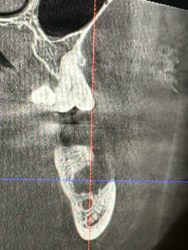

So here is the result from the surgery. I was actually pretty surprised how simple it was. I will say, the soft tissue around where the infection had eaten through the bone and was into the soft tissue was a monster to try and detach from the periosteum. Anyways, here’s how it ended up. Pretty good result imo. We placed the mixture you…

Question about the bone graft-which mix would you use in a case like this and how long for healing time? I assume 4-6 months, she’s an older pt so I’d lean more toward 6 probably but wanted to see how long you typically let the graft sit.